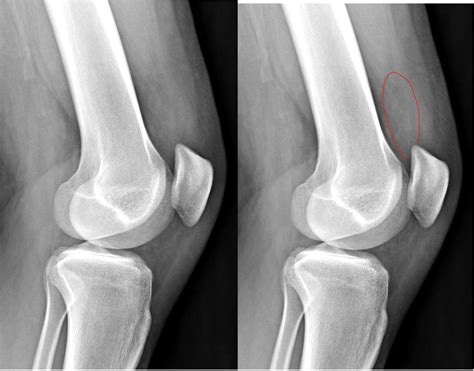

To determine the cause of your small knee effusion, a healthcare professional will typically conduct a physical examination. They will check your range of motion, test the stability of your ligaments, and look for “bogginess” or tenderness around the patella.

| X-rays | Excludes bone fractures or severe arthritis. |